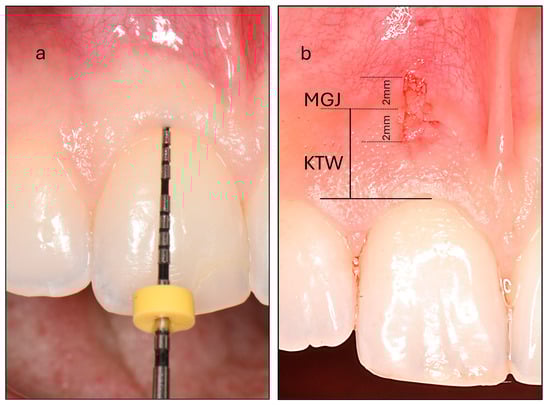

- Probe Visibility (PV): Participants were categorized into thin and thick PV groups based on the visibility of a periodontal probe through the gingiva after its insertion into the gingival sulcus (Figure 1). Intra-examiner reproducibility was evaluated prior to the study through duplicate assessments of thirty maxillary incisors performed 15 days apart, yielding a high Cohen’s kappa coefficient of 0.870.

- Keratinized Tissue Width (KTW): This was measured as the distance between the mucogingival junction (MGJ) defined using the wrinkling method and the zenith of the free gingiva of one maxillary central incisor. A periodontal probe was positioned parallel to the sagittal plane, and a standardized photograph was taken with a camera aligned to the participant’s frontal plane. The image was subsequently analyzed using specialized image analysis software (ImageJ) and KTW was digitally measured following calibration (Figure 1).